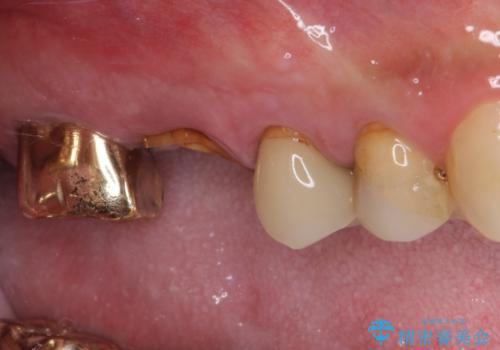

- 咬んだときに奥歯に痛みを感じるとのことで来院された患者様です。

診査の結果、左側は奥歯2本、右側は1本の抜歯が必要であることが分かりました。

抜歯となった歯は全て神経が抜かれた歯であり、強大な咬合力によって破折したことが原因で抜歯となりました。